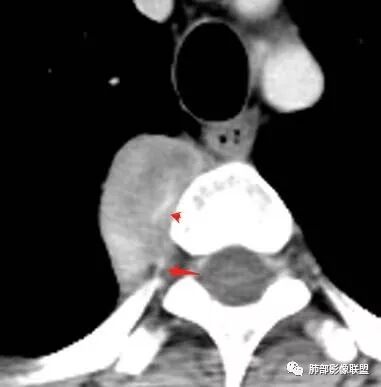

这个病例定位肺外没问题,病灶呈宽基底,见明显的胸膜掀起征,定位胸膜或右后纵隔来源,而且肿块提示肋间动脉穿行,脏层胸膜来源可能性不大(脏层胸膜由肺动脉及支气管动脉供血),那就是壁层胸膜跟纵隔来源,但是图像上有2个层面是胸膜外间隙有受压推移,所以壁层胸膜来源也不考虑;病灶是渐进性强化,常见的就是间叶来源含有梭形细胞的软组织肿瘤跟后纵隔常见的神经源性肿瘤鉴别,那如何在后纵隔的大山里拨开云雾找到我们想要的答案呢?那小编在这里先理出几个问题:

问:这个病例病灶确实邻近椎间孔生长,除了神经源性肿瘤会向椎间孔方向生长,还有什么肿瘤会有这种行为?这个病灶整体形态呈扁平不规则,周围骨质未见破坏,就一定是良性吗?    答:这个病灶明显嵌入式生长,往往提示病灶柔软或有侵袭性,而神经鞘瘤往往有包膜,有张力,典型的形态往往呈类圆形、“逗点形”或“哑铃型”横向延入某一椎间孔内;神经节细胞瘤虽然可以比较柔软,但是具有大量粘液基质,动静脉期强化不明显,延迟强化轻度增强,加之没有钙化,故符合点不多;此外比较柔软的肿瘤如淋巴瘤,但是周围没有肿大淋巴结不太考虑;本例形态不规则的实性肿块,没有明显骨质破坏,倾向具有侵袭性的间叶来源的肿瘤。

病灶内的肋间动脉穿行代表什么?

答:代表病灶内供血血管或病灶具有侵袭性将血管包绕其中。提示病灶的肺外来源属性。